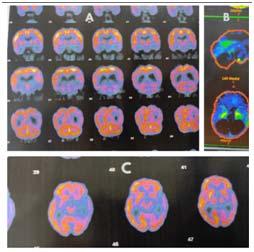

Routine blood investigations, ECG, chest Xray, CT scan and MRI of the face (including orbits) and brain were done (Fig 1).

Fig 1 — Pre-operative and Postoperative coronal MRI slice